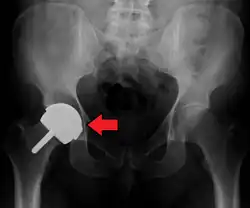

Dislocation

Dislocated artificial hip

Liner wear, particularly when over 2 mm, increases the risk of dislocation.[15] Liner creep, on the other hand, is normal remoulding.[16]

Dislocation (the ball coming out of the socket) is one of the most common complications. Hip prosthesis dislocation mostly occurs in the first three months after insertion, mainly because of incomplete scar formation and relaxed soft tissues.[15] The chance of this is diminished if less tissue is cut, if the cut tissue is repaired and if large diameter head balls are used.[17] Surgeons who perform more operations tend to have fewer dislocations. Important factors which are related to dislocation are: component positioning, preservation of the gluteal muscles and restoration of leg length and femoral offset.[18] Keeping the leg out of certain positions during the first few months after surgery further reduces risk.